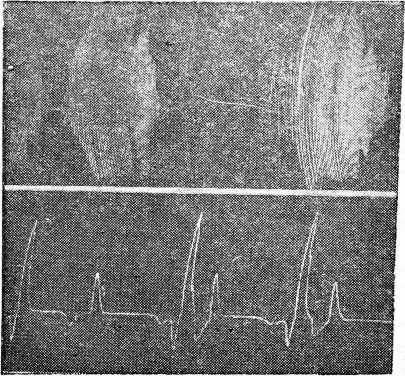

Рис. 1. Типы дыхания Чейн-Стокса (верхние три кривые). Форма неполного Чейн-Стокса (нижняя кривая).

Рис. 2. Типы дыхания Биота (левые три кривые). Формы волнообразного дыхания (правые три кривые).

Для характеристики вышеизложенного представляем кривые типичных форм периодического ритма дыхания с промежуточными и редкими формами, полученные нами в эксперименте на животных (рис. 1, 2, 3,) и схему расстройств ритма дыхания.

Рис. 3. Альтернирующий Чейн-Стокс (верхняя кривая) Альтернирующее дыхание (нижняя кривая).